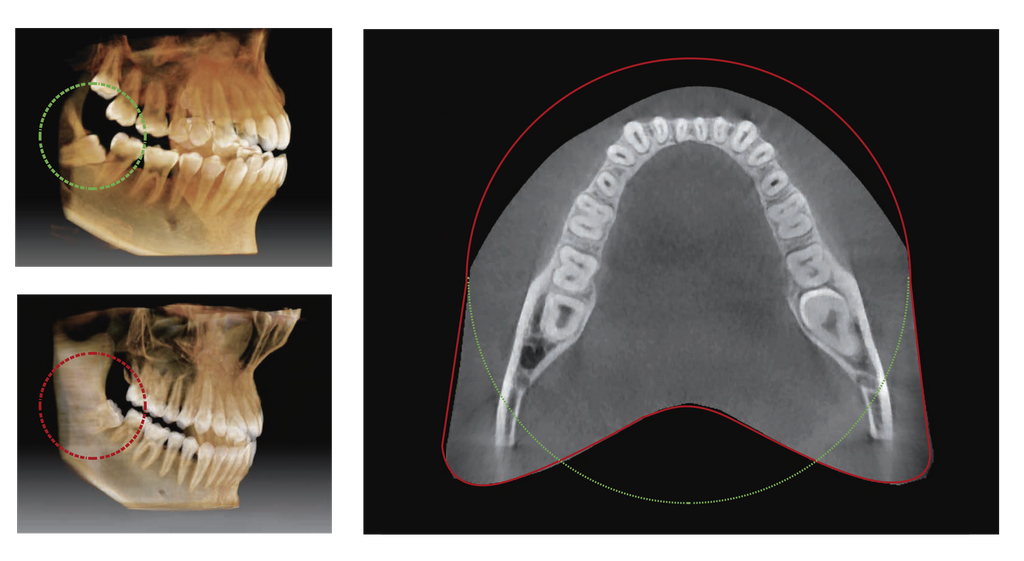

El FOV de Vatech A9 proporciona un volumen anatómico en forma de arco que muestra una visión más amplia de la dentición en comparación con otros equipos con el mismo FOV.

Cuando el diente está inclinado, existe una alta posibilidad de que esta pieza se corte de la imagen.

El «FOV anatómico» elimina esta posibilidad muestra el área oculta de la dentición.